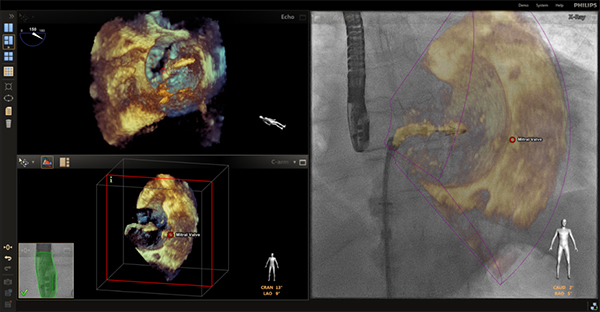

エコーナビゲータ –SHD(心構造疾患)治療の際のLiveX線(透視)とLive Echoを重ねたイメージガイダンス-

エコーナビゲータは,SHDと呼ばれる心臓構造疾患への経カテーテルデバイス治療において,エコーと血管撮影装置を結びつけ,双方の情報をリアルタイムに連動可能です。透視中にエコープローブを映しこむだけで位置情報を認識するため,位置あわせのためのレジストレーション操作は不要です。SmartFusion機能により透視像とエコー画像をリアルタイムにフュージョン,適切に確度の高いナビゲーションを可能にするインターベンショナルツールです。